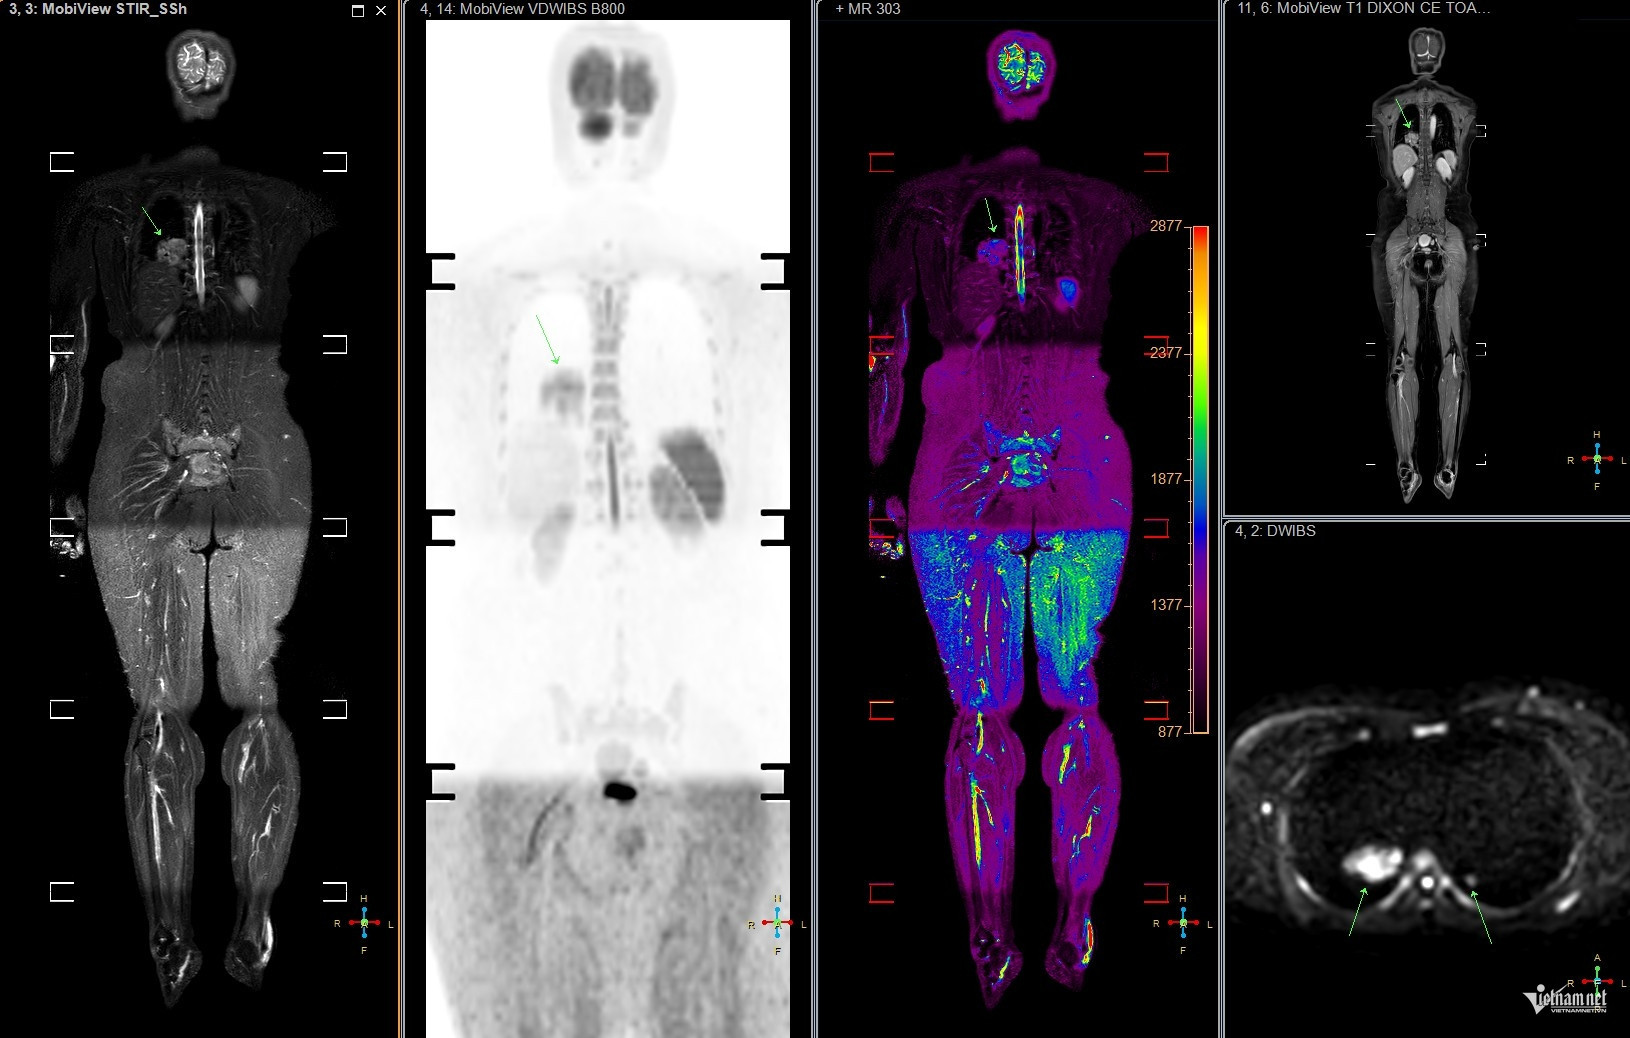

Tại bệnh viện, sau khi thực hiện các xét nghiệm và chụp chiếu, bác sĩ phát hiện chị T. có khối u ở phổi và các nốt mờ ở xương do di căn. Kết quả này khiến vợ chồng chị và bạn bè thân thiết bàng hoàng. Nhìn vào tấm phim MRI, từng nốt mờ ở phổi và xương được bác sĩ chỉ rõ, những lời giải thích như khắc sâu vào tâm trí chị.

Về việc tầm soát sớm ung thư phổi, giáo sư Khoa cho biết những người có yếu tố nguy cơ như hút thuốc lá chủ động, thụ động có thể thực hiện qua chụp CT liều thấp, giúp phát hiện tổn thương nhỏ. Các kỹ thuật hiện đại như PET, PET/CT, PET/MRI, kết hợp với sinh học phân tử, hỗ trợ xác định đột biến gene, từ đó chọn phương pháp điều trị trúng đích.

Ung thư phổi thường có đặc điểm di căn sớm. Hiện nay, các phương pháp điều trị bao gồm phẫu thuật, xạ trị, hóa trị, liệu pháp miễn dịch và điều trị đích, mang lại nhiều hy vọng cho bệnh nhân.